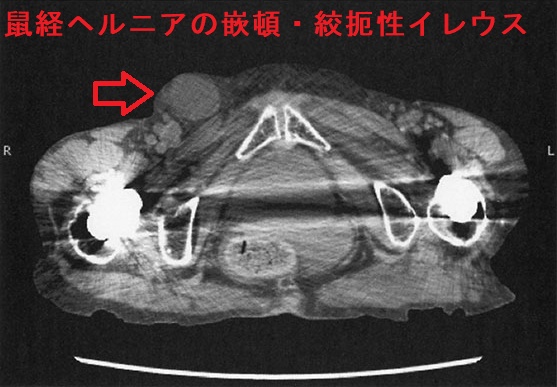

外鼠径ヘルニア(間接鼠径ヘルニア)では、腸管が内鼠径輪→鼠径管を経て外鼠径輪に脱出。陰嚢腫大は外鼠径ヘルニア特有の症状です。内鼠径ヘルニアに比べてヘルニア門が狭く嵌頓(かんとん)しやすい。

CT画像でヘルニア門が下腹壁動脈の外側なら外鼠径ヘルニア、内側なら内鼠径ヘルニアです。